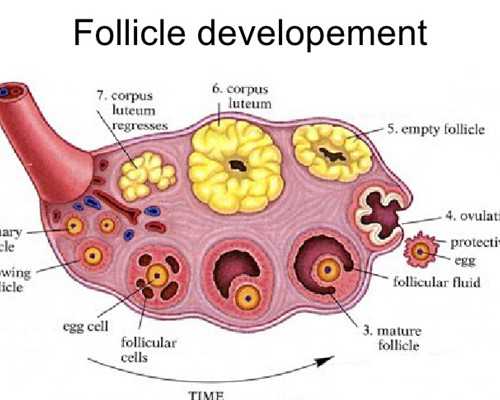

這當(dāng)中主要原因是卵子質(zhì)量與卵巢功能的退化而引起,再加上環(huán)境污染、輻射、化學(xué)品等多種不良因素影響,卵子質(zhì)量無時(shí)不刻的發(fā)生著退化與改變。

美國(guó)試管嬰兒恩西諾分院RobertBoostanfar[羅伯特布斯坦福]說:據(jù)多年臨床調(diào)查,卵巢的儲(chǔ)備功能在30-35歲以后便開始迅速下降。同時(shí),如果在35歲之前曾有多次懷孕流產(chǎn)、第一胎不健康經(jīng)歷,更會(huì)增加二胎風(fēng)險(xiǎn)和不孕不育的幾率。

? ? 對(duì)于高齡女性生育的困難,泰國(guó)試管嬰兒會(huì)根據(jù)高齡女性的身體情況制定適合的方案,合理促排,科學(xué)使用促排卵藥物控制性促排,減少對(duì)女性身體的傷害,這樣即使是高齡生育也不會(huì)對(duì)身體有太多的傷害,取得高質(zhì)量的卵子,增大試管嬰兒的成功率。在促排時(shí)會(huì)嚴(yán)格監(jiān)控和及時(shí)調(diào)整,在卵泡發(fā)育成熟及時(shí)取出,獲得多顆卵子,因?yàn)楦啐g生育的女性卵泡少,所以科學(xué)促排非常重要。